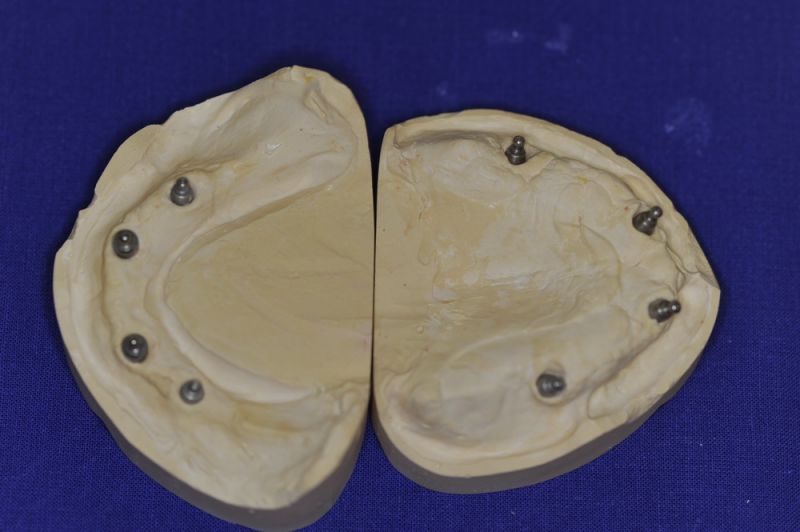

Patient aus der Region Eckernförde erhält neue implantatgestützte Cover Denture Prothesen

Der Patient erhält heute eine neue implantatgetragene Prothesenrekonstruktion im Ober- und Unterkiefer.

Das Einkleber der O-Ring-Abutments, etwas euphemistisch als "chair-side" beschrieben entwickelte sich zu einem schweißtreibenden Abendvergnügen.